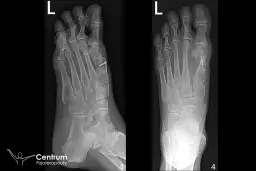

- Konsultacja kwalifikacyjna i badania wstępne: Przed zabiegiem niezbędna jest wizyta u ortopedy, który oceni stopień deformacji, zleci niezbędne badania (np. RTG stopy) i zakwalifikuje pacjenta do operacji. Te wstępne kroki są kluczowe dla bezpieczeństwa i skuteczności leczenia.